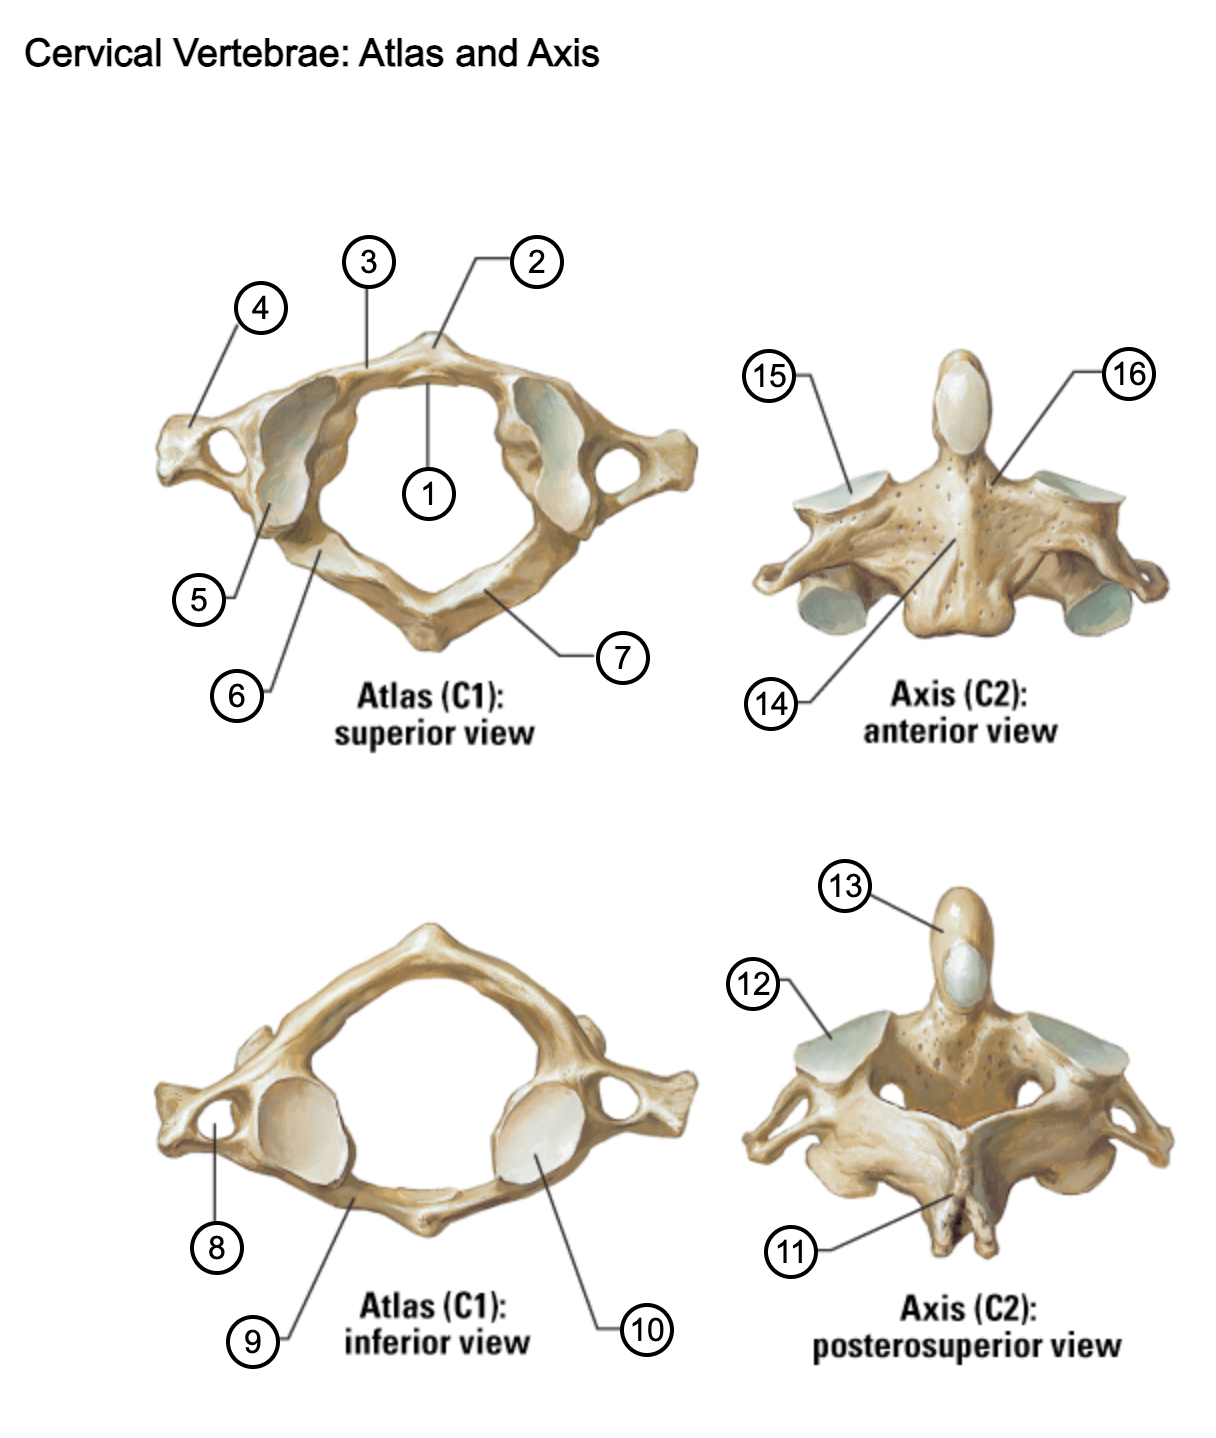

1

facet for dens

2

anterior tubercle

3

anterior arch

4

transverse process

5

superior articular surface of atlas

6

groove for vertebral artery

7

posterior arch

8

transverse foramen

9

anterior arch

10

inferior articular surface of atlas

11

spinous process

12

superior articular facet

13

dens of axis

14

body of axis

15

superior articular facet for atlas

16

pedicle of vertebral arch